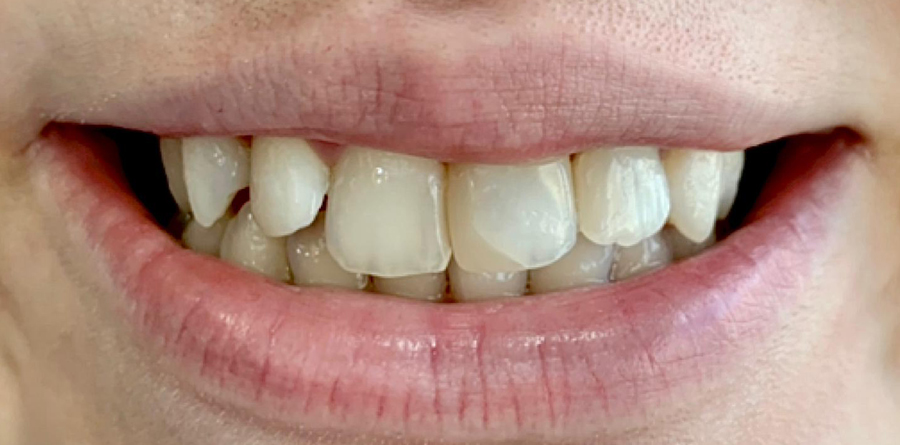

Vorher Nachher